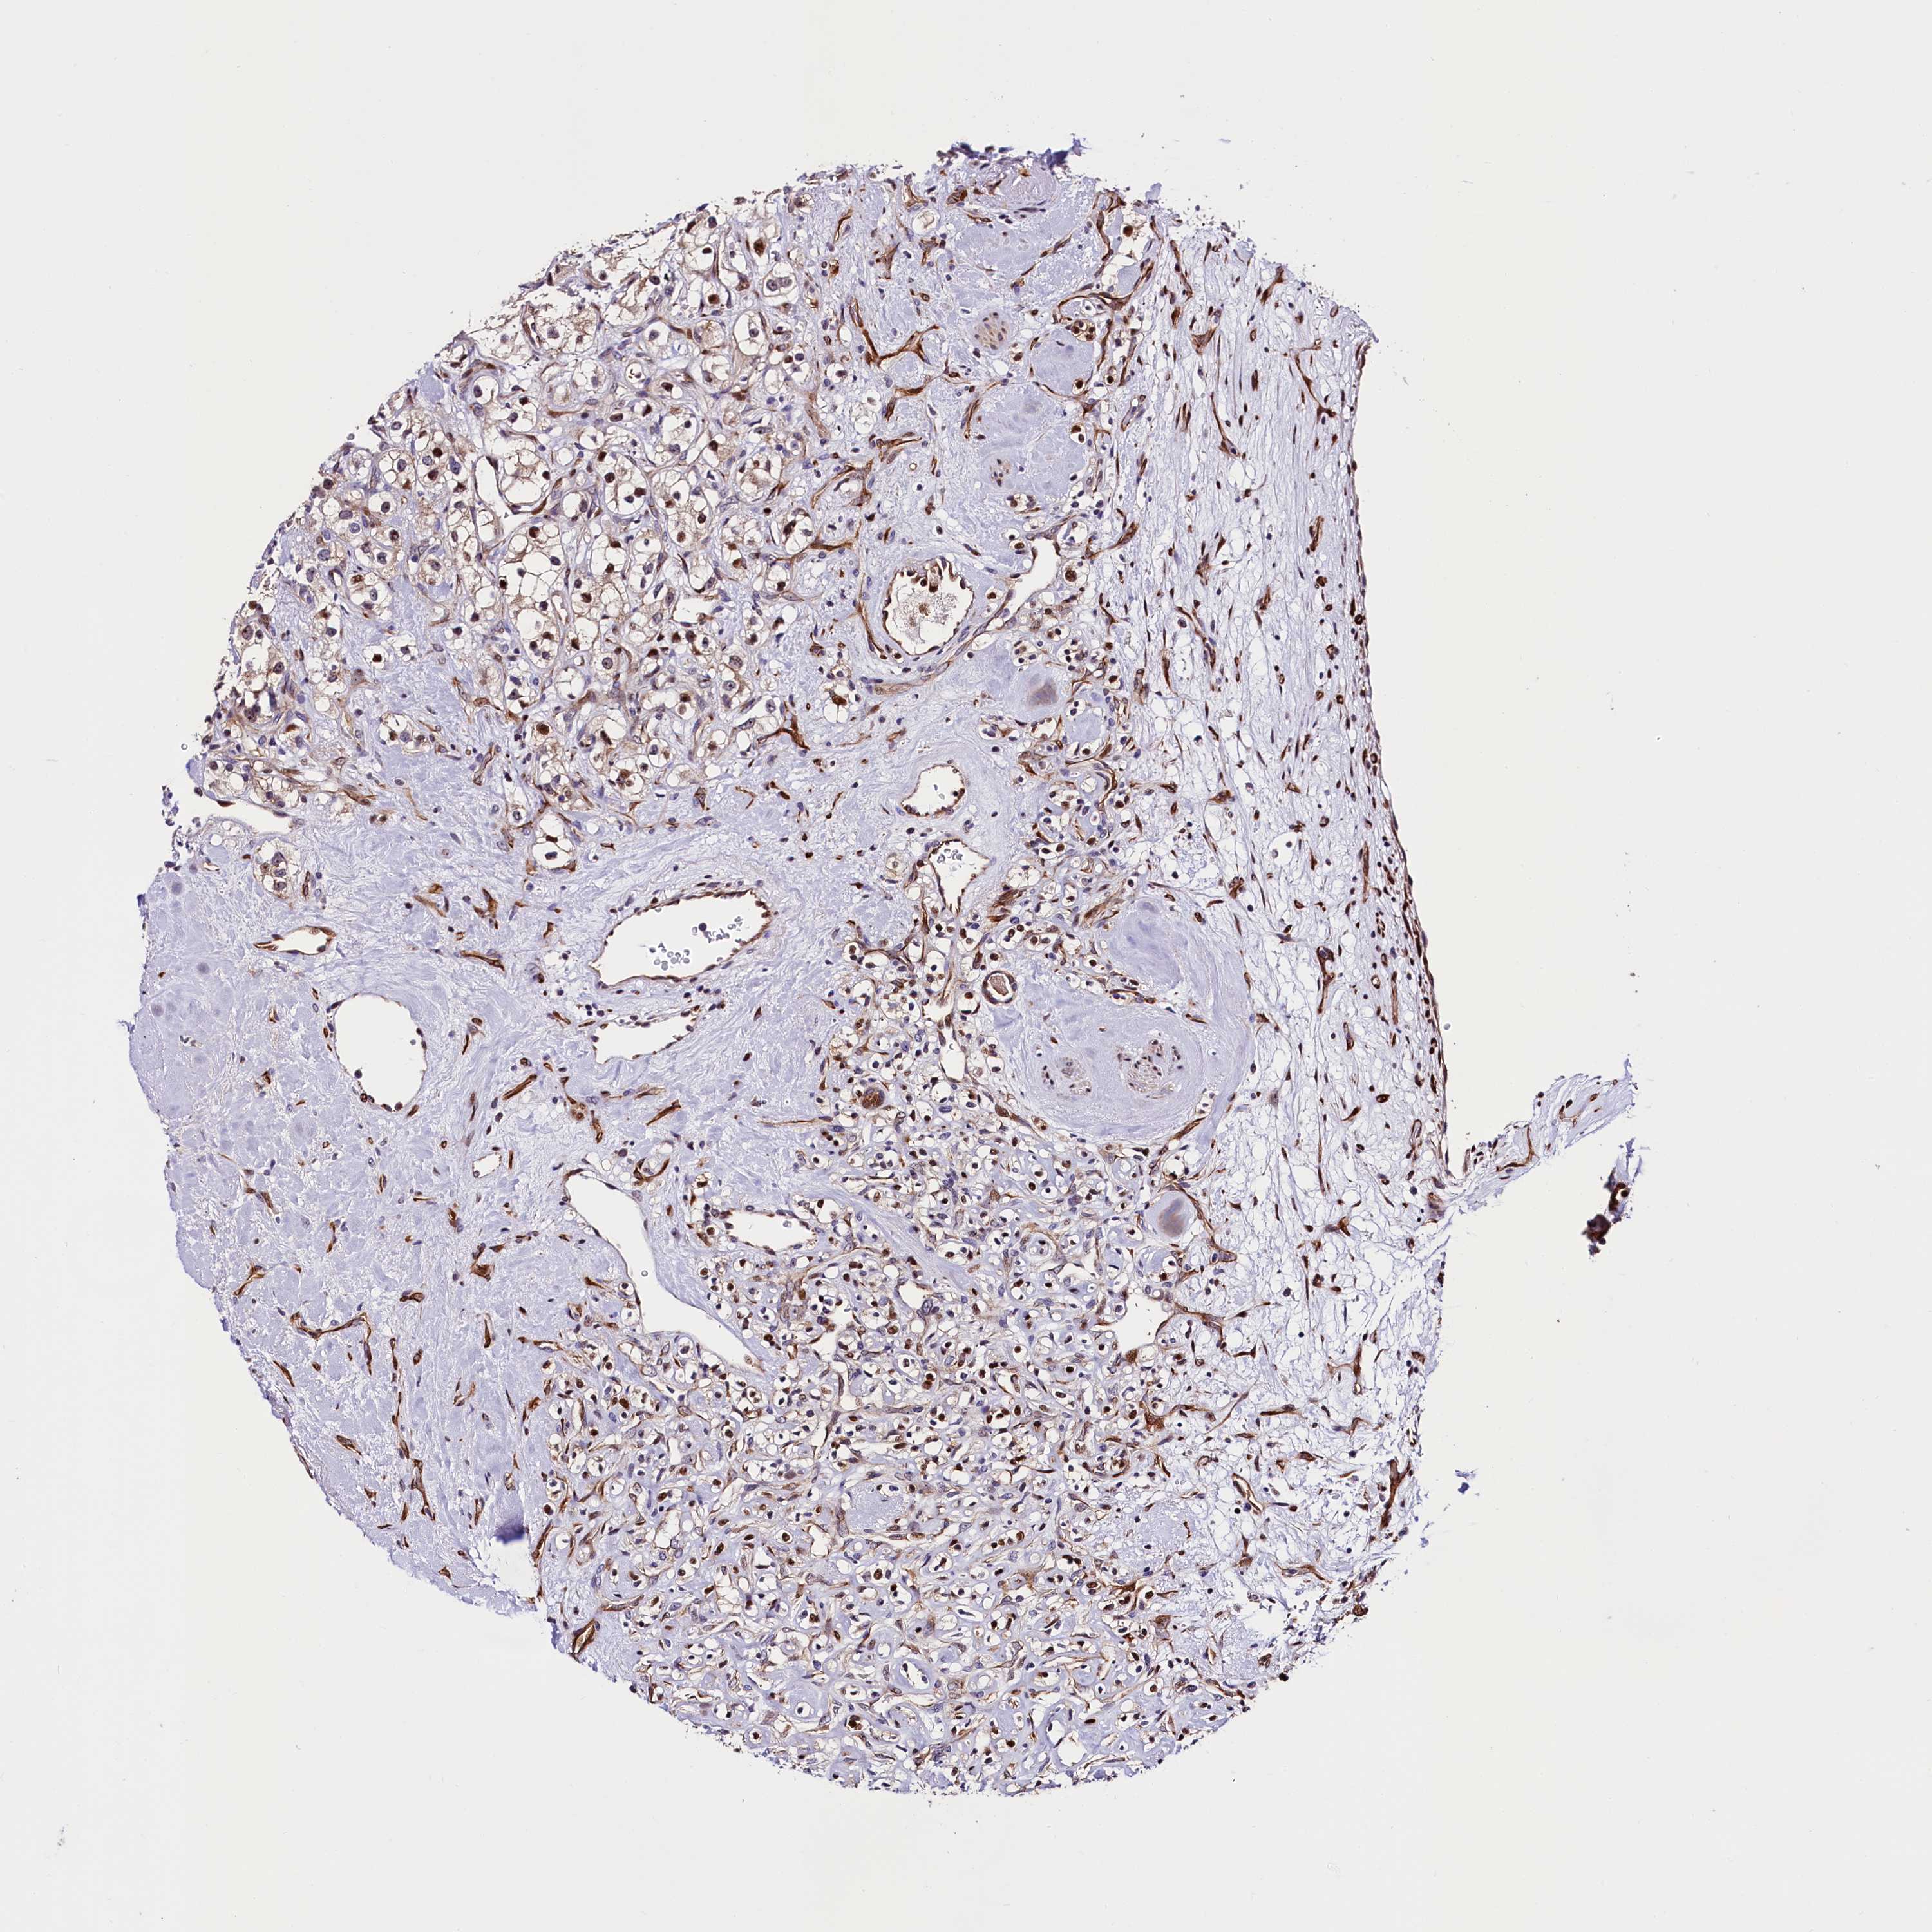

CANCER RENAL CANCER Show tissue menu

KICH TCGA KIRC TCGA KIRC VALIDATION KIRP TCGA PROTEIN RCC CPTAC PROTEIN EXPRESSION